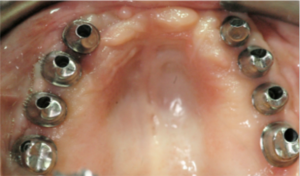

Case 2

Maggie is a 55-year-old woman who has been living with an ill-fitting upper denture (plate) since her early 20s and finally got fed up with it. She wanted a new and improved Hollywood smile transformation. She was recently divorced and wanted to get on with her life, socialize, travel, and meet new people. Her daughter found Dr. Veisman online after a fruitless search in her home province, Newfoundland. She flew many times back and forth to Toronto until the treatment was completed. She decided to proceed with 8 implants in the upper jaw with a fixed final restoration so she would not have to ever remove her teeth.

Before

After